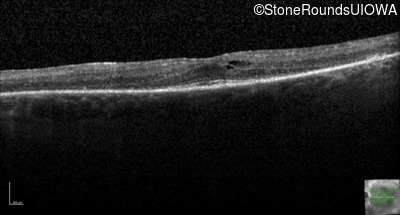

Optical Coherence Tomography - Left - 20/25 -1

Exemplar / OCT Stack

OCT Stack